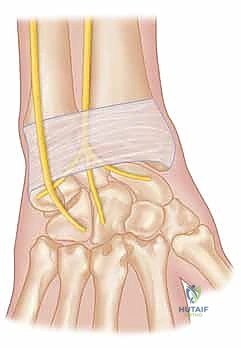

Image

FIG 3 • The still photographs shown have been captured from a fluoroscopy video of a wrist with ulnocarpal instability during the supination test. A. Top of the examination cycle with the wrist in neutral position. B. Bottom of the examination cycle. In both images, the black line represents the distance between proximal edges of pisiform and triquetrum. The red line indicates the length of the triquetrum. The shorter length of the red and black lines in B compared with A demonstrates the ulnocarpal instability present during dynamic testing.